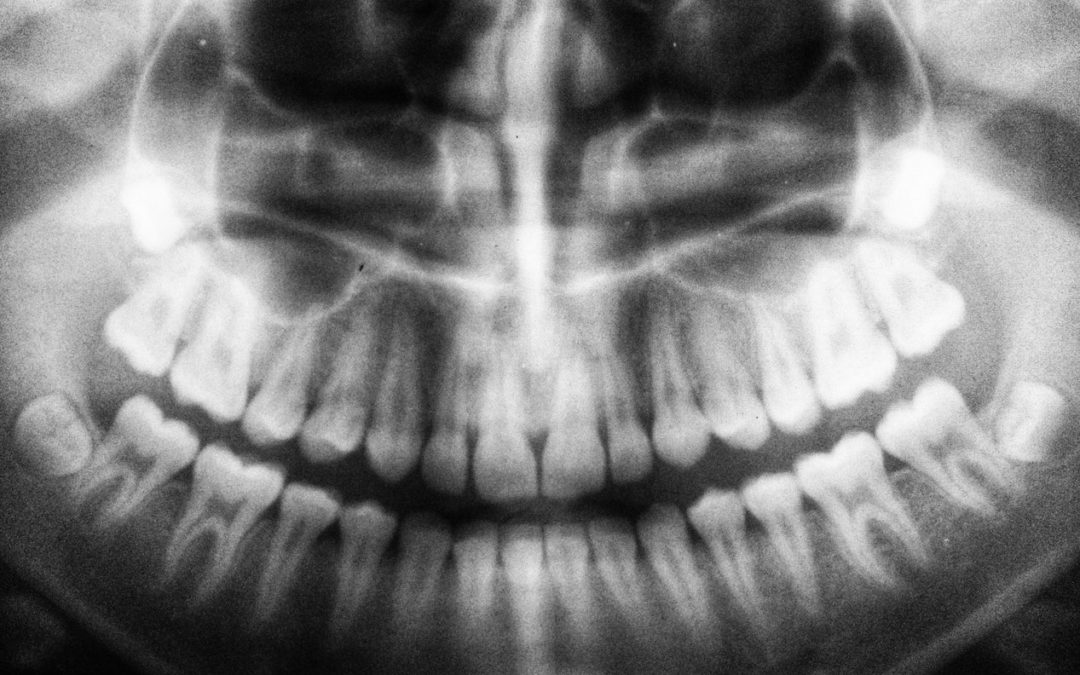

A Variety Of Reasons To Get An X-Ray – Rancho Cucamonga Dentist

Rancho Cucamonga Dentist say, dental X-rays are a critical part of any oral care plan. They are normal in the dentistry universe. Anyone who has ever visited their dental hygienist has likely had them taken at some point. The Dental X-Ray Process - Rancho Cucamonga...